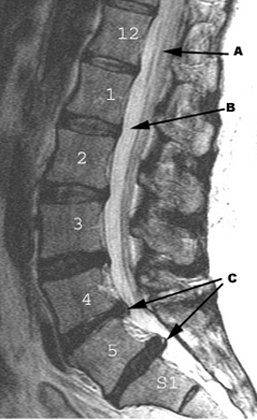

Osteoarthritis Herniated Discs

• A: Distal cord and nerve roots

• B: CSF

• C: Herniated discs L4-L5 and L5-S1